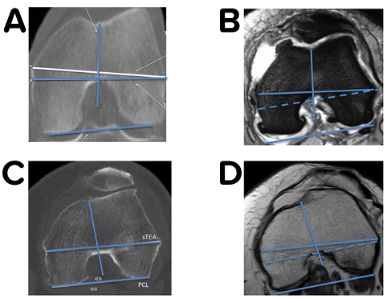

More than 25 years ago Rich Berger performed the first CT evaluation of a painful, not well functioning TKA which showed normal frontal and sagittal radiographs. Based on this experience he published the basics for the axial plane analysis for painful TKA using CT imaging technique [4]. This was followed by the classical paper on the clinical relevance of malrotated components in TKA evaluated with his CT evaluation protocol [5] (Fig 1).

Without knowing all the details of this complex 3-D biomechanics of the patellofemoral joint, Insall has recommended to realign the prosthesis to the extensor mechanism during TKA surgery already 40 years ago. He introduced the tibia tubercle axis (TTA) for rotational alignment (Fig 21) which brings the TT under the trochlea from extension until deep flexion in all cases [1]. Most surgeons follow this simple technique but never thought about the wide variation of the TT to the proximal tibia anatomy. During the last decade several studies using 3-D imaging have shown that proximal tibia axial deformity is common in TKA patients and the TT position to the proximal tibia anatomy is very variable [22,30,48]--. Furthermore, it could be demonstrated that in varus knees external torsional deformities showed a clear correlation to the severity of the frontal malalignment [52]. The most commonly used measurement technique for knees with TKA is the anterior tibia tubercle angle (ATTA), which measures the angle between two lines (Fig 1 B and C) [4,30].